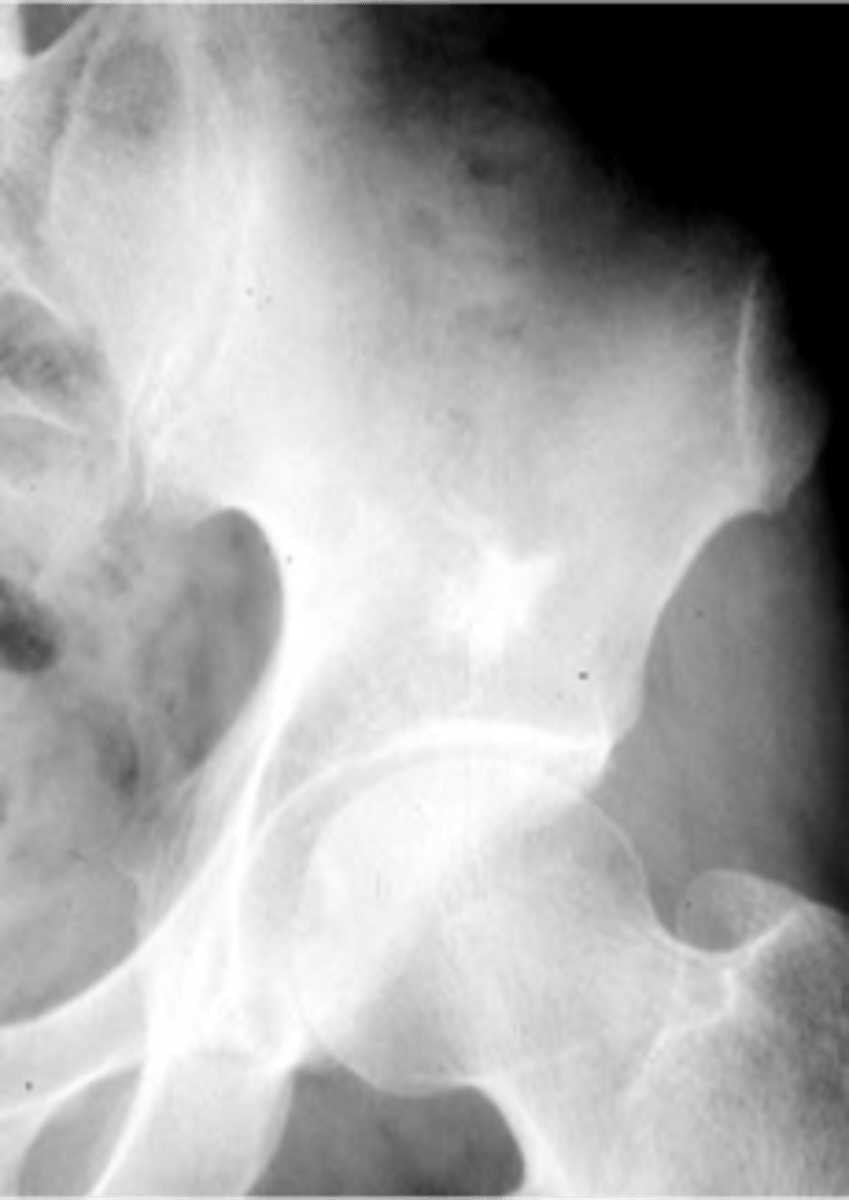

Giant cell tumor pathology:

- _____ benign (F:M, 3:2)

- _____ malignant (M:F, 3:1)

<p>Giant cell tumor pathology:</p><p>- _____ benign (F:M, 3:2)</p><p>- _____ malignant (M:F, 3:1)</p>

3

New cards

- 20-40 y.o.

- Knee (tibia and femur)

- Localized pain and aching

- Joint pain and restricted motion

State the clinical features of giant cell tumor

<p>State the clinical features of giant cell tumor</p>

4

- Osteolytic

- Geographic

- Multiloculated and septated

- Begin in metaphysis

- Extend to subarticular bone

- Expansion

- Eccentric

- Quasi-malignant (can't tell benign from malignant)

State the imaging features of giant cell tumor

<p>State the imaging features of giant cell tumor</p>